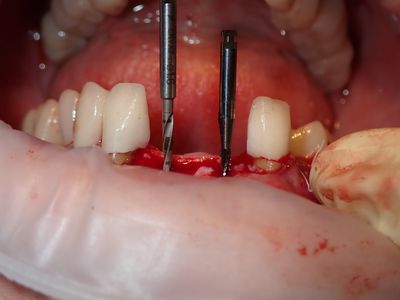

NSankhyan - immediate 13, impls 1121 and 25 with grafting

13 exo, loss of labial plate, implant placed buccal region grafted with sticky bone and collagen membrane soaked in prf fluid. 11/21 limited Labial-palatal width of bone, ridge split to 5mm, osteotomies prepared to about 2mm, remainder with densah drills, implants placed with ample bone, buccal grafted with same sticky bone. densah drills used for apical portion of 25 implant, soft bone, implant placed